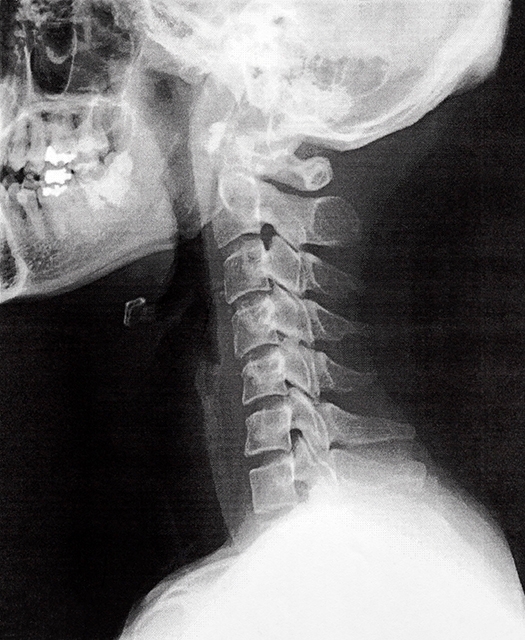

頚椎ヘルニアの確定診断には画像診断が不可欠です。医療機関にて行う以下のような技術が用いられます。

- X線撮影: X線は骨の状態を確認するために使用されますが、椎間板自体は映らないため、ヘルニアの診断には補助的な役割を果たします。